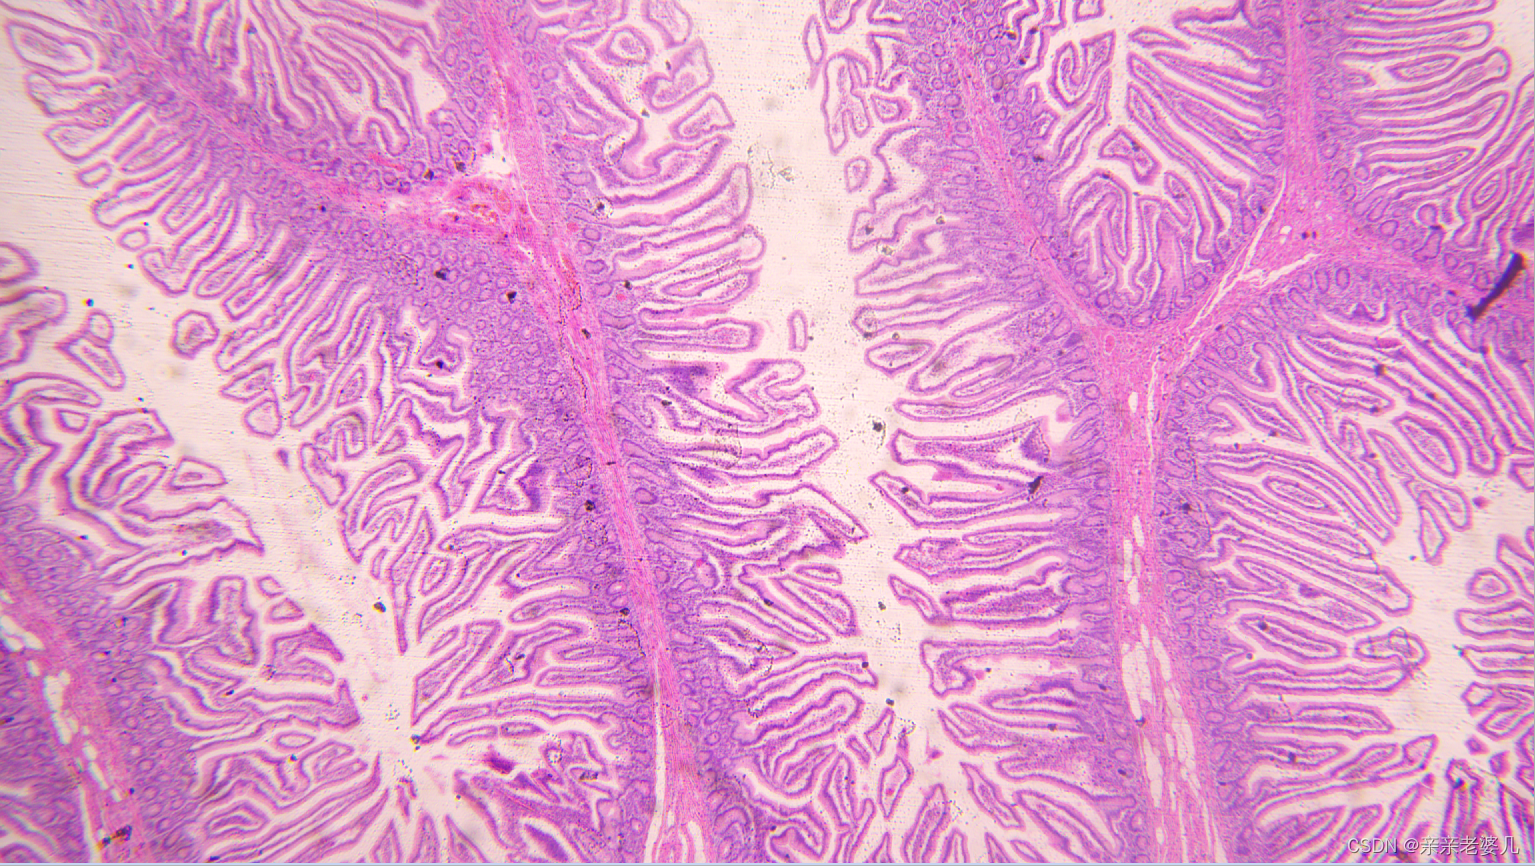

9. 千奇百怪的疾病——疾病的显微诊断及大体实物标本展示

如何获得标本:

手术 取材 包埋 蜡块 切片 染色

肠腺癌

肺水肿

肝癌

宫颈鳞癌

正常大肠

正常肺

正常肝

正常小肠